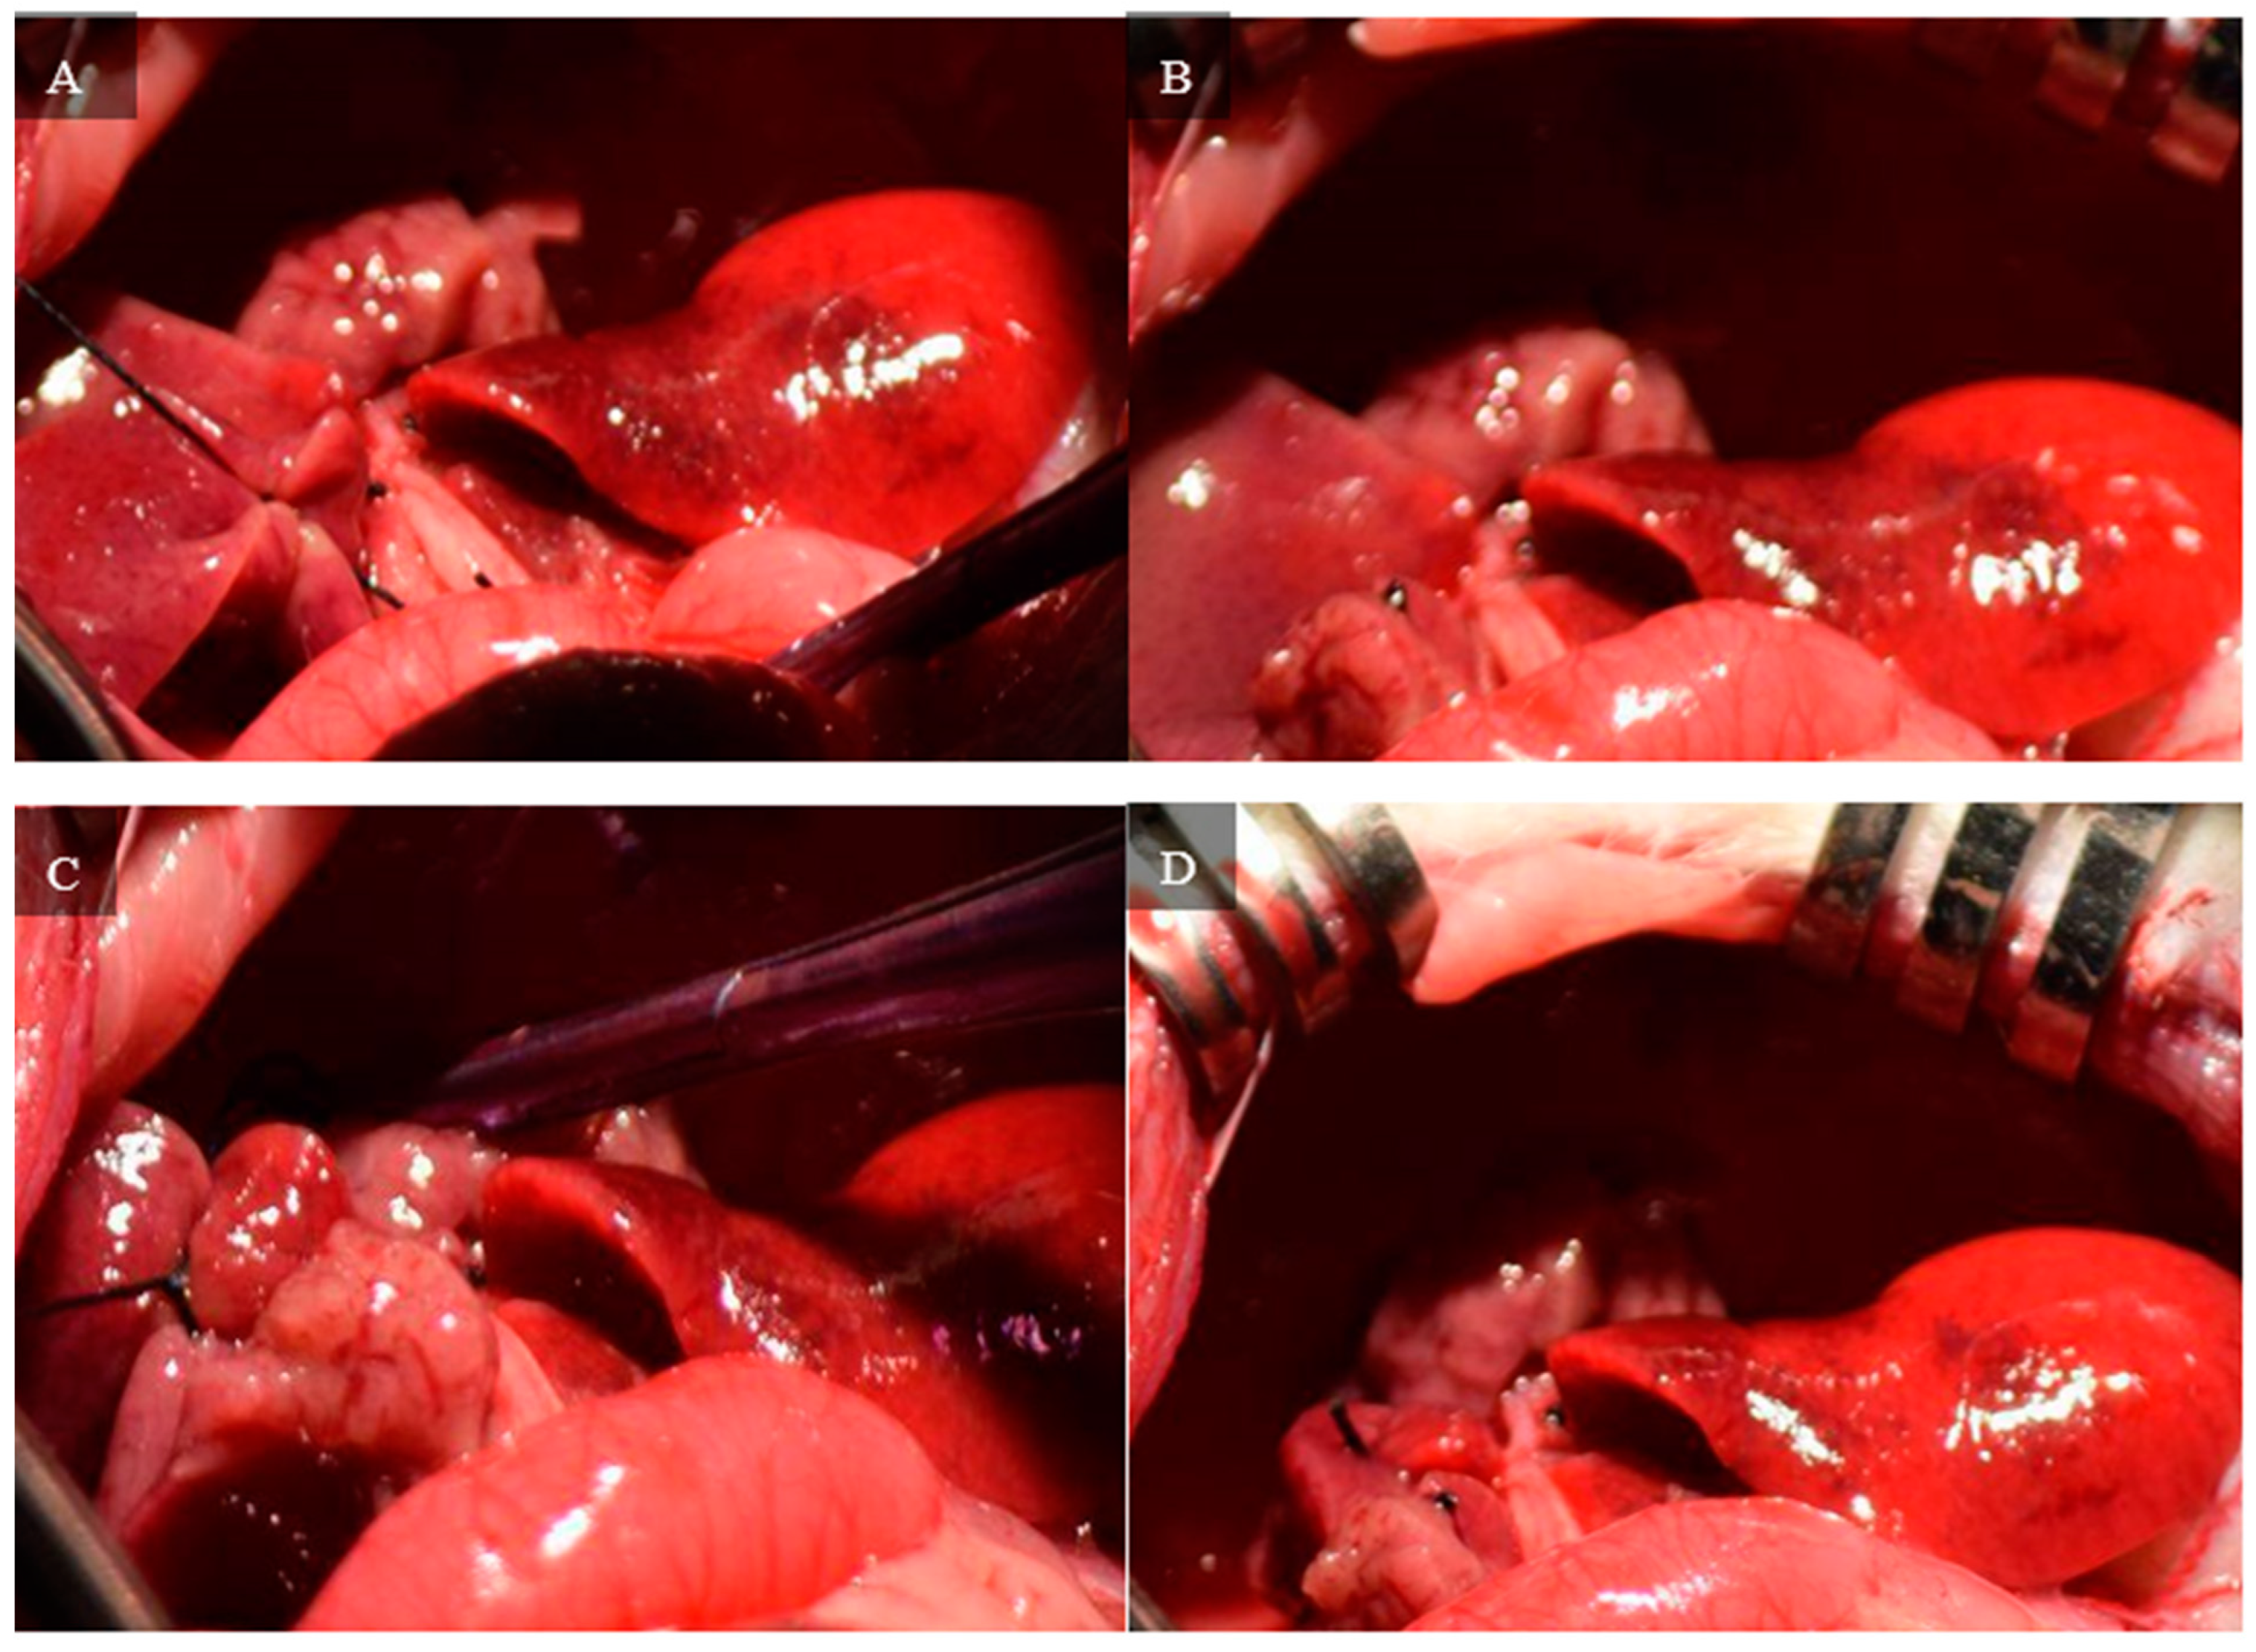

A second dissection of the hilum is required to control the inflow to the right superior and right inferior lobes. The branch of the hilum that supplies the right lateral lobe is isolated. Similar to the initial dissection, the membrane separating the bile duct and hepatic artery is penetrated with curved jaw micro needle holders, and 4-0 silk thread is passed through. One end of the thread is placed through the membrane between the portal vein and inferior vena cava, so the thread only holds the portal vein and hepatic artery. The portal vein and hepatic artery are ligated with 4-0 silk thread, and visual confirmation of successful ligation can be seen by a color change in the right superior and right inferior lobes. Figure 6 depicts the steps of this portal ligation.

Figure 6. (A) 4-0 silk thread is passed between the bile duct and hepatic artery on the portion of the hilum that supplies the right lateral lobes. (B) One end of the thread is passed between the portal vein and inferior vena cava, so the thread holds the hepatic artery and portal vein. (C) The portal vein and hepatic artery are ligated. Visual confirmation of successful ligation is seen by the color change in the right superior and right inferior lobes.